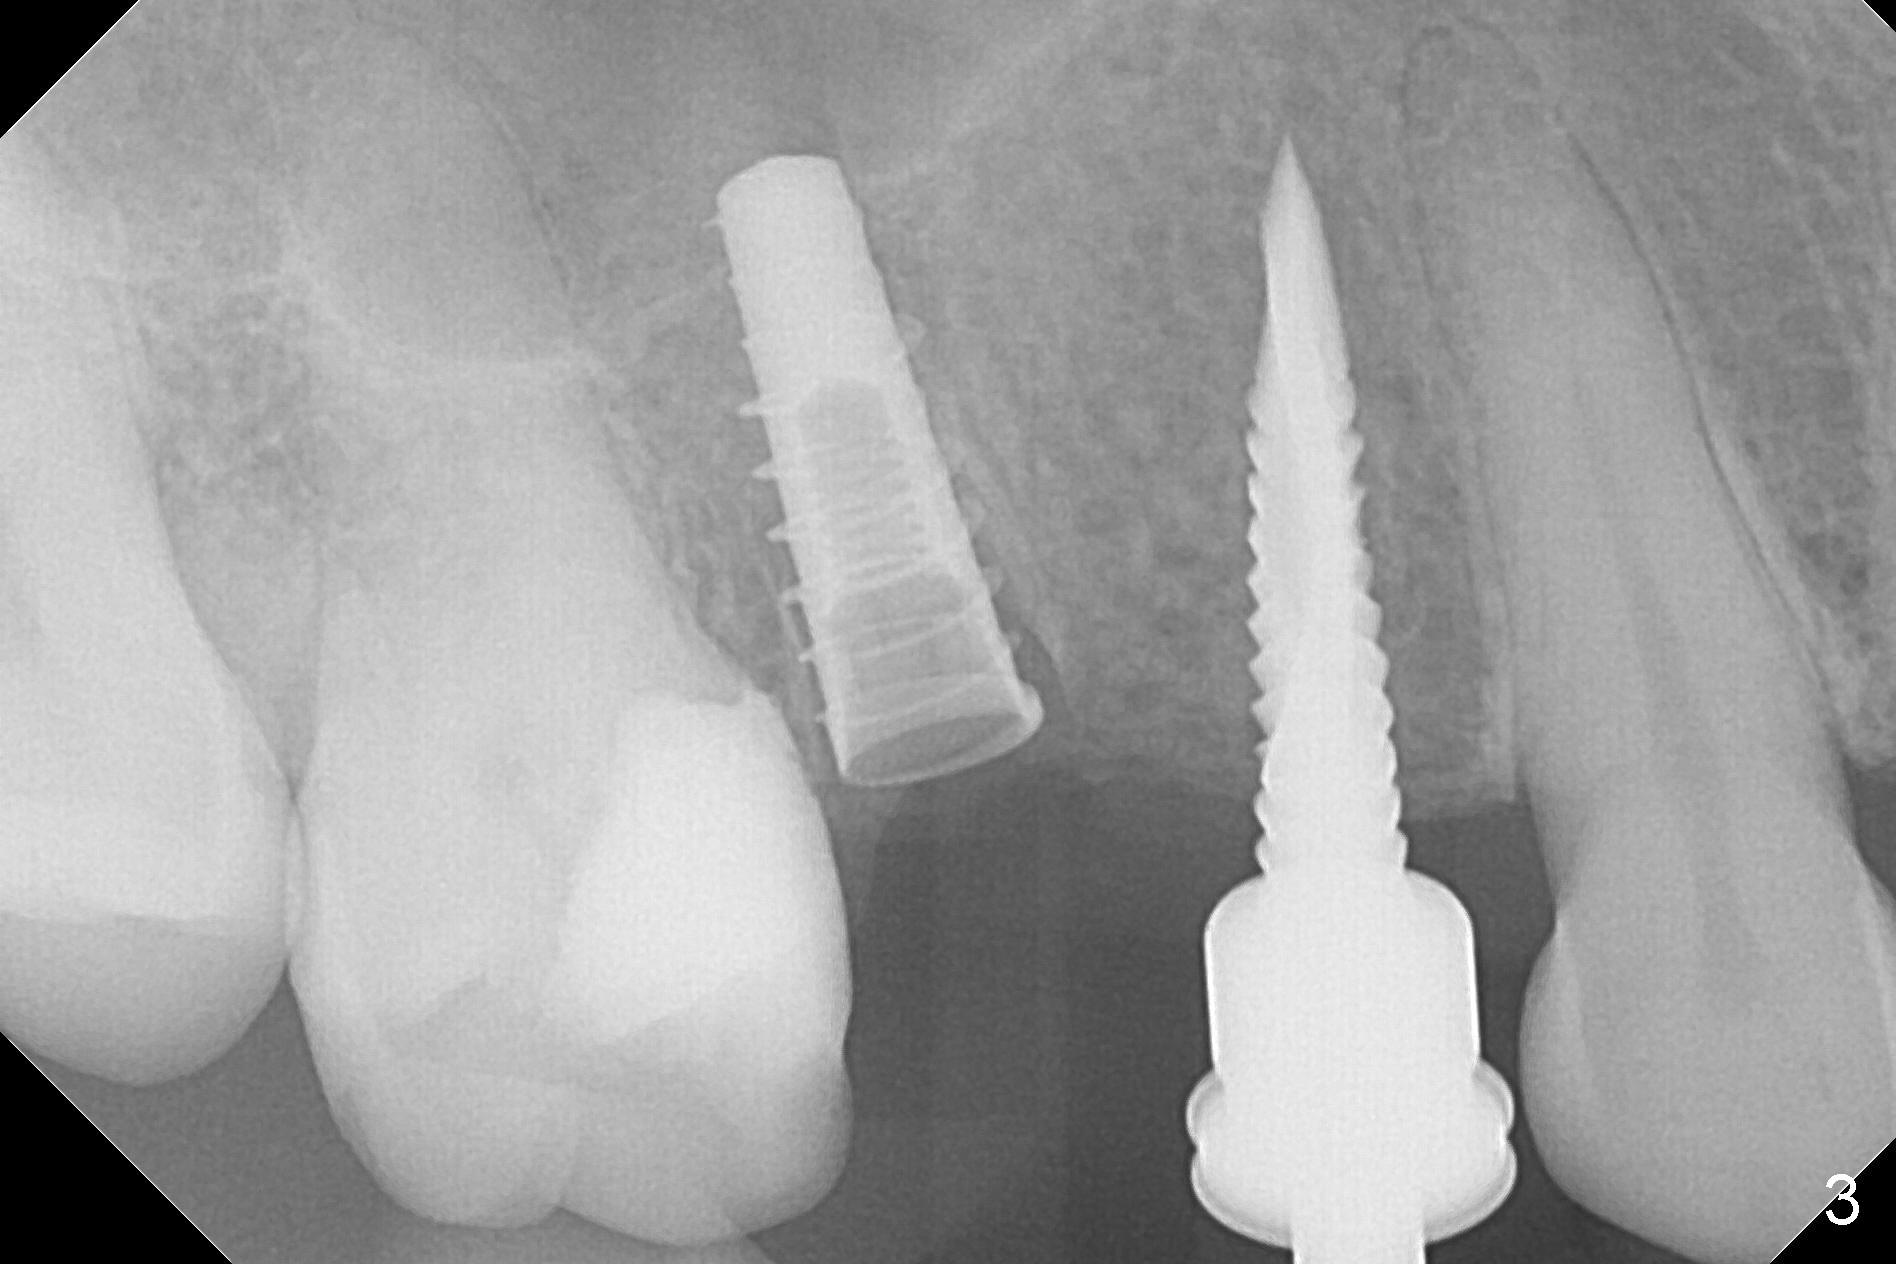

The buccal plate of the socket of #4 is thin and short (Fig.1, 5B (coronal section of the socket) red area) with apical perforation (Fig.5B >). Osteotomy at #4 starts with 1.6 mm drill in the palatal slope (Fig.2 circle; Fig.5C blue arrow), while that at #5 with Magic Split (Fig.2 black line). In fact sinus perforation occurs with the 1.6 mm drill. Osteotomy increases by using Magic Drills sequentially (2.8 and 3.3 mm) at #4 and Magic expander (3.0 mm) and the same Magic Drills at #5 (Fig.3). A 4x11 mm dummy IBS implant is placed with insertion torque of 45 Ncm at #4 with apparently intruding into the sinus (Fig.3). When a 4.5x9 mm implant is placed, the insertion torque is actually reduced (<35 Ncm, Fig.4). As osteotomy or implant diameter enlarges, it shifts buccally with less bone contact buccally (Fig.5D, as compared to Fig.5C)). In brief, once a dummy implant has achieved a reasonably high stability, do not over seat it. A small immediate implant may have more solid bone contact.

At the healed site (#5), insertion torque of a 4x11 mm implant is >50 Ncm (Fig.4). Because of supraeruption of the tooth #28 (Fig.6 arrow), a healing abutment (4x2 mm) is placed at #5 (data not shown), while a pair abutment (4.5x4(2) mm) is placed at #4 (Fig.4,6). In fact a splinted provisional is placed at #4 and 5 with a low occlusal table. There is no apparent bone loss 1 years 5 months postop (Fig.7). In fact the implants either perforate the palaatal or buccal (B) plate, as revealed by CBCT (1 year 6 months postop, immediately post cementation, Fig.8,9). It appears necessary to have guided surgery and smaller implant in the narrow ridge.